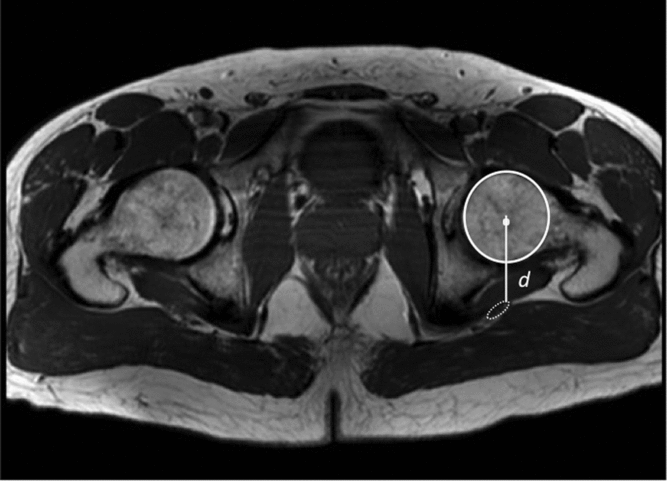

The distance between the center of the femoral head and the sciatic nerve was measured on retrospective review of MRI images of the pelvis by one of the co-authors (LP), who is an experienced musculoskeletal radiologist. Images were obtained from adults who already had imaging for other reasons. A circle was drawn at the level of the femoral head, and the center point of the femoral head was marked. The distance from the center of the femoral head to the sciatic nerve (r) was obtained by drawing a line from the center of the femoral head to the sciatic nerve. This was performed for both hips on each image (Figure 2). Distances were recorded, along with age and gender. This study was approved by the Sunnybrook Health Sciences Centre Research Ethics Board.

Figure 2: Axial T1 weighted MR image of both hips. A circle was drawn at the level of the femoral head, and the distance to the sciatic nerve was measured from the center of the femoral head by drawing a line posteriorly to the front margin of the sciatic nerve. This was performed for both hips.

The distance between the center of the femoral head and the center of the sciatic nerve was measured in 20 adults (11 women and 9 men). The median distance was 41.0 mm (interquartile range = 38.0–45.9 mm) (Table 1). Distances in men (mean = 44.1 mm) were significantly greater than in women (mean = 39.9 mm) (p < 0.04) on both sides. Left and right distances were highly correlated with each other (r = 0.97, p < 0.001), but there was no correlation with age in this group of adults. Using the distance above, to approximate the length of segment B in Figure 2,

one obtains a median length of 64 mm (interquartile = range 60–73 mm). This is the predicted length of nerve required to accommodate hip flexion.